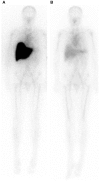

The phylogenetically ancient, pentraxin family of plasma proteins, comprises C-reactive protein (CRP) and serum amyloid P component (SAP) in humans and the homologous proteins in other species. They are composed of five, identical, non-covalently associated protomers arranged with cyclic pentameric symmetry in a disc-like configuration. Each protomer has a calcium dependent site that mediates the particular specific ligand binding responsible for all the rigorously established functional properties of these proteins. No genetic deficiency of either human CRP or SAP has been reported, nor even any sequence polymorphism in the proteins themselves. Although their actual functions in humans are therefore unknown, gene deletion studies in mice demonstrate that both proteins can contribute to innate immunity. CRP is the classical human acute phase protein, routinely measured in clinical practice worldwide to monitor disease activity. Human SAP, which is not an acute phase protein, is a universal constituent of all human amyloid deposits as a result of its avid specific binding to amyloid fibrils of all types. SAP thereby contributes to amyloid formation and persistence in vivo. Whole body radiolabelled SAP scintigraphy safely and non-invasively localizes and quantifies systemic amyloid deposits, and has transformed understanding of the natural history of amyloidosis and its response to treatment. Human SAP is also a therapeutic target, both in amyloidosis and Alzheimer's disease. Our drug, miridesap, depletes SAP from the blood and the brain and is currently being tested in the DESPIAD clinical trial in Alzheimer's disease. Meanwhile, the obligate therapeutic partnership of miridesap, to deplete circulating SAP, and dezamizumab, a humanized monoclonal anti-SAP antibody that targets residual SAP in amyloid deposits, produces unprecedented removal of amyloid from the tissues and improves organ function. Human CRP binds to dead and damaged cells in vivo and activates complement and this can exacerbate pre-existing tissue damage. The adverse effects of CRP are completely abrogated by compounds that block its binding to autologous ligands and we are developing CRP inhibitor drugs. The present personal and critical perspective on the pentraxins reports, for the first time, the key role of serendipity in our work since 1975. (345 words).